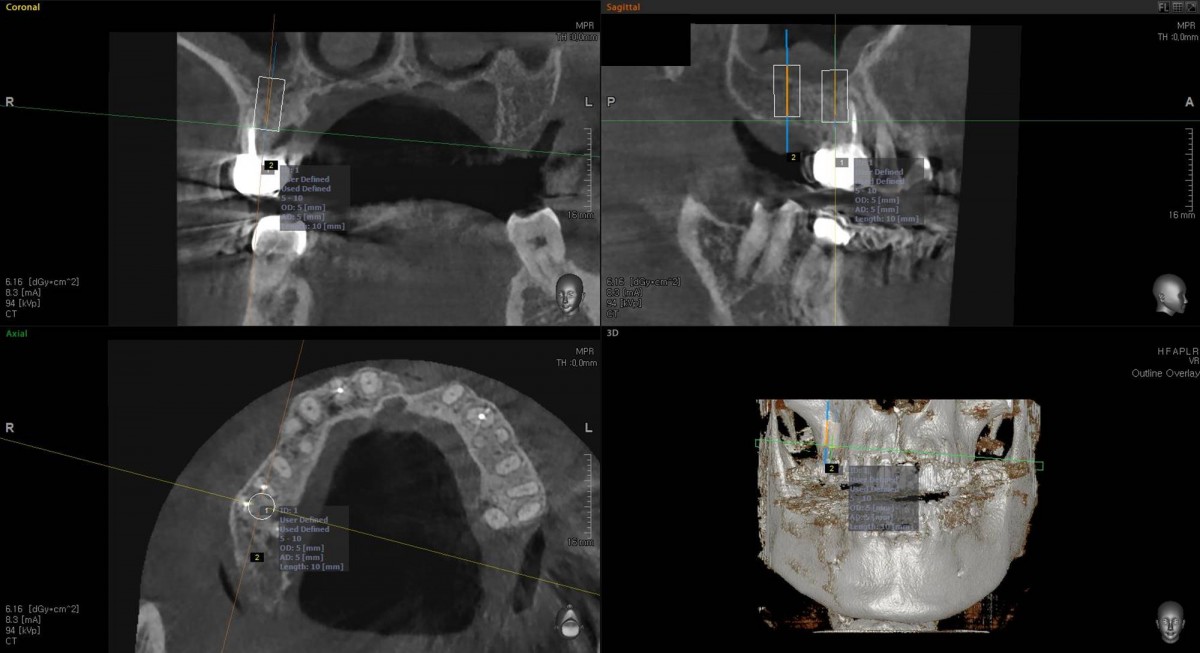

Socket Lift and Implant Placement in the right maxilla.

<GCacg> A 56-year-old male patient complained of pain in the right upper and lower jaws. And he wanted the upper first molar to be pulled out first.